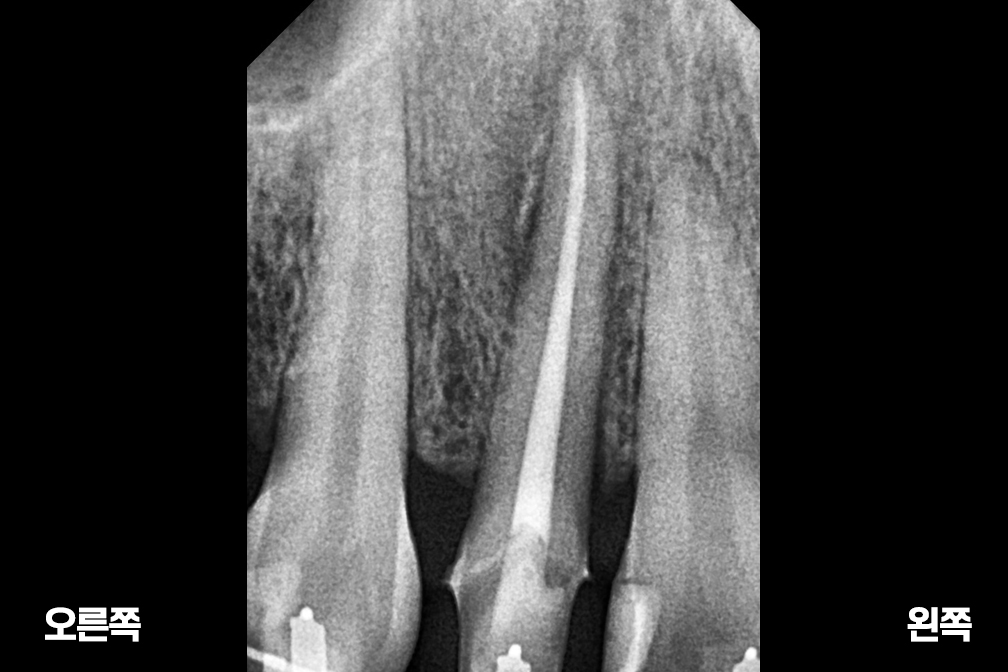

After 2026년 1월 21일